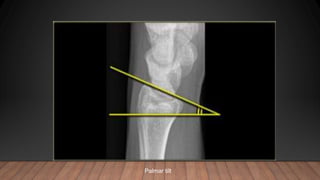

• Palmar radial tilt :The plane of the radial articular surface slopes downwards

and forwards (average 11°).

Palmar tilt